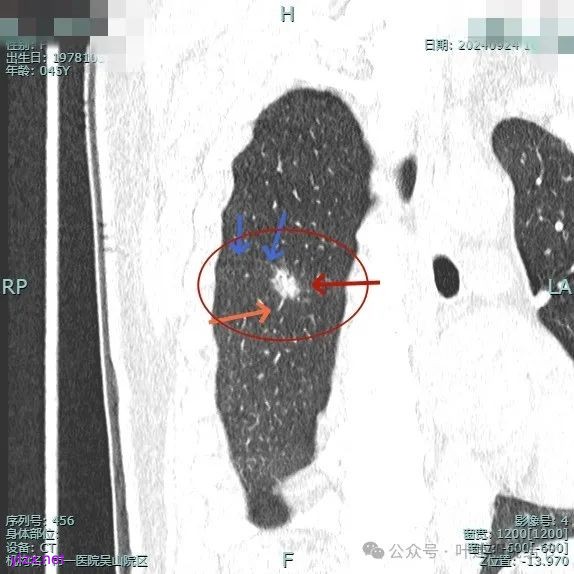

我们先来看2024年9月时的影像:

病灶1:

右下背段混合密度病灶,边上不太清爽,有片状淡磨玻璃影,实性部分密度较高。

感觉病灶有点晕征似的,表面不平,灶内不太致密。

有小血管进入,似有晕征。

离胸膜近但牵拉不明显,病灶边缘有细毛刺,较短且不太锐利。

边缘少许磨玻璃成分,血管进入明显。

瘤肺边界稍显不清。